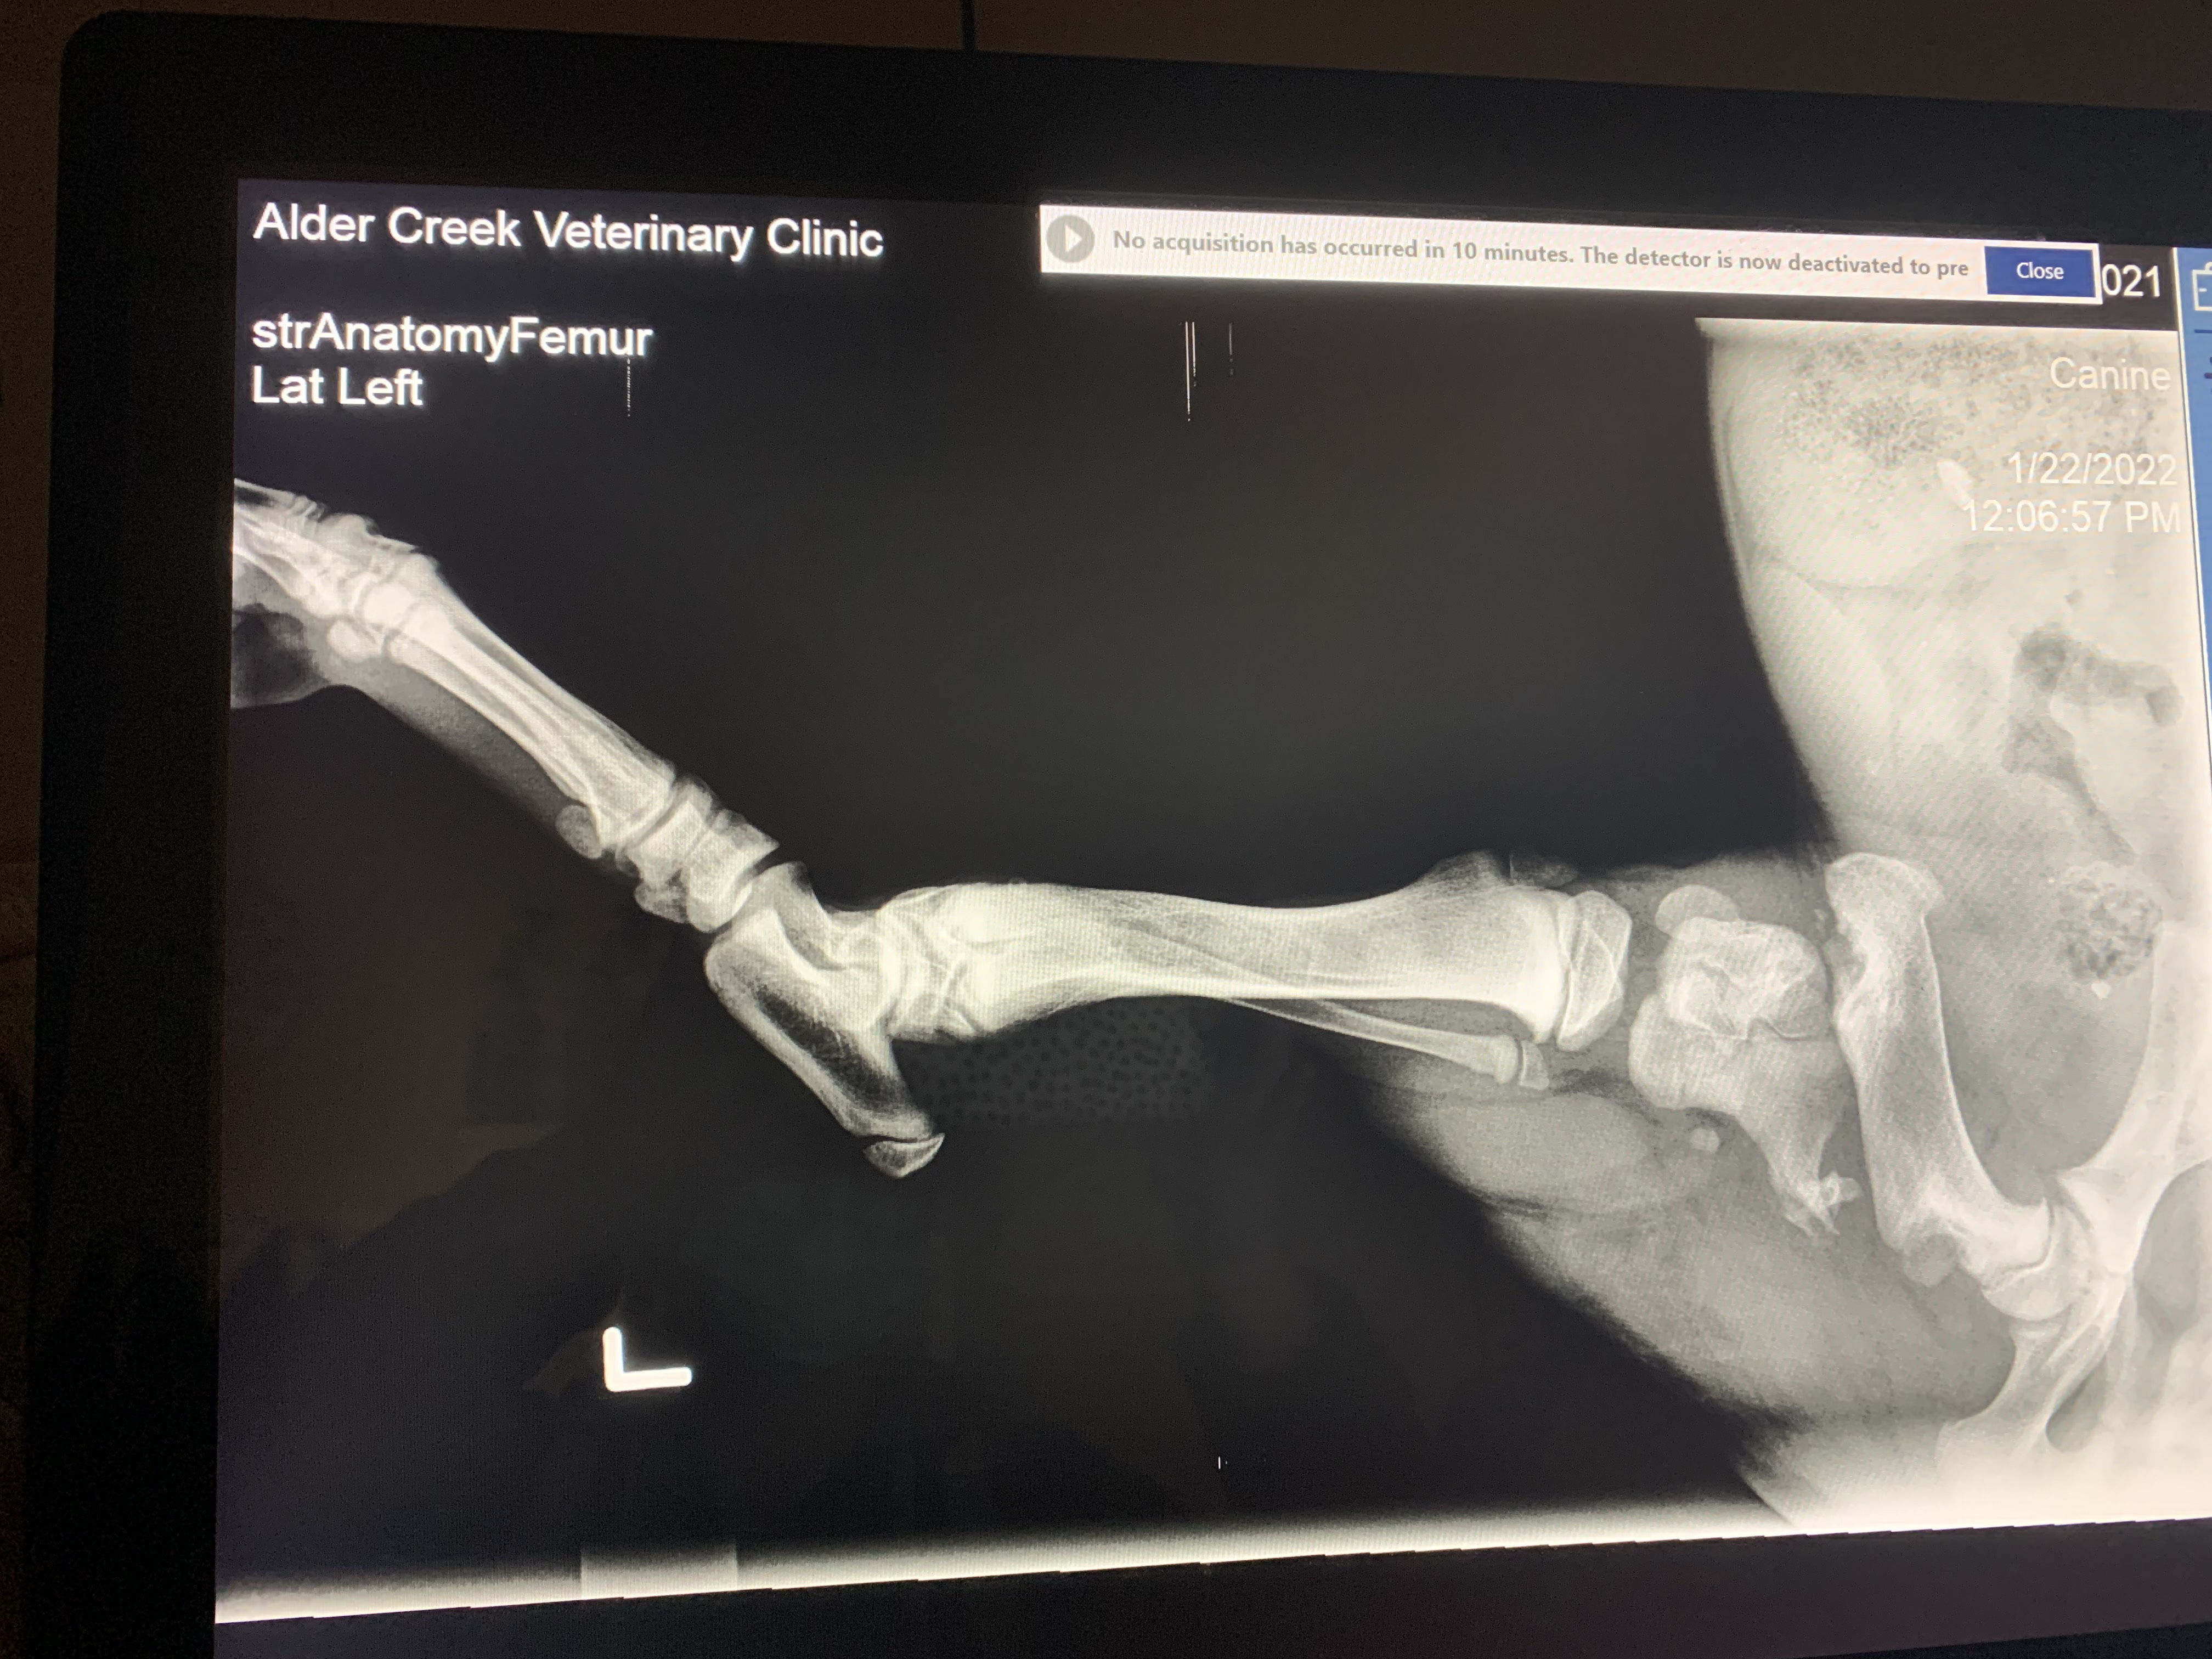

They said put this dog down the surgery will be too much money and she might still lose her leg. Luckily the owner wasn't going to take that for an answer but she didn't know what to do so she relinquished this sweet pup to a person who has too big of a heart. After countless calls and chatting with several overbooked veterinarians, we found a group called Surgery 4 Pets. They have agreed to squeeze Lucky into a surgery spot on Valentine's Day. This group is going to give it their all to save this sweet girls leg. However that does come at a cost. We are asking for the price of a box of chocolates to help support Lucky's operation. $10, $20 whatever little amount you can offer will 💯 go towards Lucky's surgery.